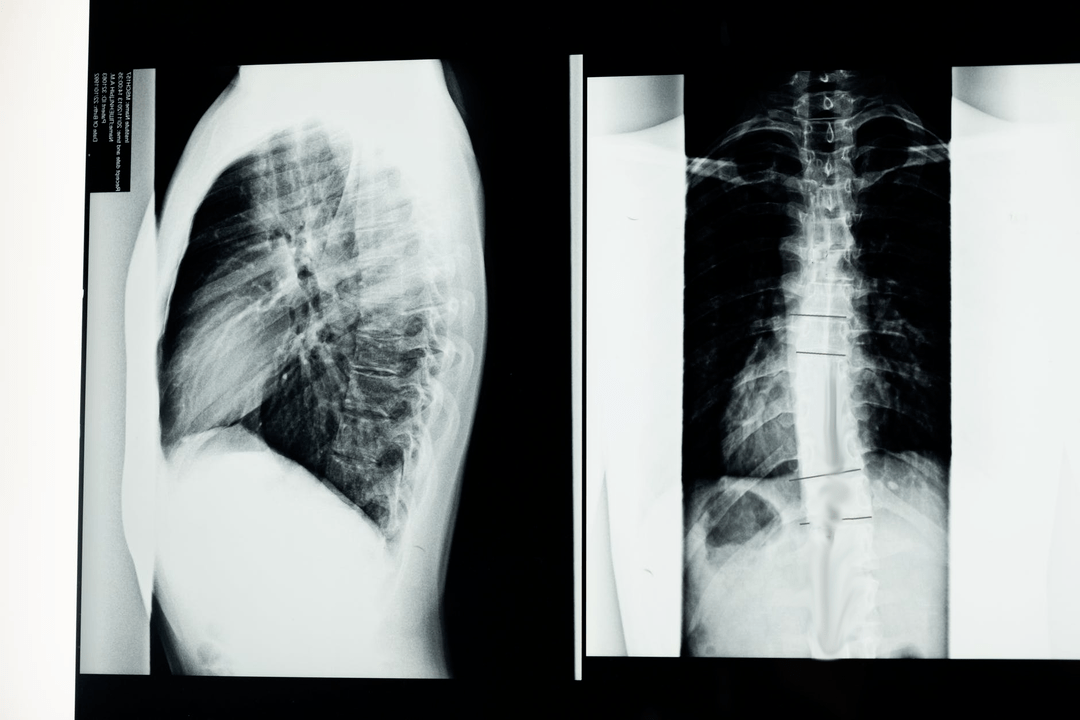

Przed rozpoczęciem badań diagnostycznych neurolog zbiera historię medyczną pacjenta i dokładnie bada jego dolegliwości. Osteochondroza ma wspólne objawy z niektórymi innymi chorobami, dlatego ważne jest, aby móc różnicować patologie. Badania rentgenowskie pomogą potwierdzić diagnozę osteochondrozy: radiografia, mielografia i tomografia komputerowa.

Badanie RTG pozwala na uzyskanie zdjęcia RTG kręgosłupa lub jego odcinka. W ten sposób lekarz może określić lokalizację dotkniętą chorobą. Dla jasności wyjaśnimy, w jaki sposób można określić osteochondrozę za pomocą prześwietlenia rentgenowskiego: obraz pokaże zwężenie krążka międzykręgowego, obecność narośli kostnych (osteofitów) lub zmianę kształtu odcinka kręgosłupa.